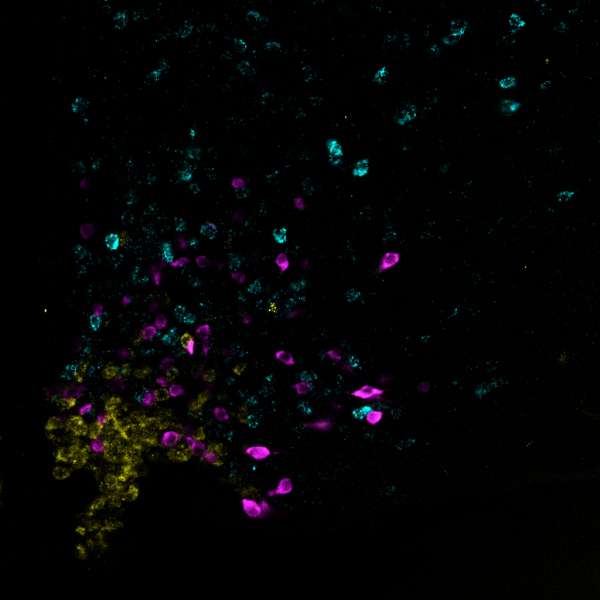

Seit den 1980er Jahren steigt die Zahl von Menschen mit Übergewicht (Adipositas) – und von damit einhergehenden Krankheiten wie Diabetes mellitus und Herzkreislauf-Erkrankungen. Forschende vom Max-Planck-Institut für Stoffwechselforschung aus dem Labor von Jens Brüning haben an Mäusen untersucht, welche Nervenzellen genau das „Überessen“ von hochkalorischer Nahrung steuern. Dazu wurden die Tiere mit einer besonders fettreichen Nahrung gefüttert und anschließend untersucht. „Schon drei Tage fettreiche Ernährung reichten aus, um erhöhte Aktivität von Nozizeptin-Neuronen in einer bestimmten Region des Gehirns, dem Nucleus arcuatus des Hypothalamus, nachzuweisen,“ so Alexander Jais, Erstautor der aktuellen Studie.

In weiteren Versuchen nutzten die Forschenden genetisch veränderte Mäuse, bei denen sich die Aktivität der Nozizeptin-Neurone im Hypothalamus mittels Licht kontrollieren lässt. „Die Aktivierung dieser Gehirnzellen führte zu einer übermäßigen Nahrungsaufnahme bei den Tieren“ erläutert Jais. „Durch die Aktivierung von Nozizeptin-Neuronen werden bestimmte, das Sattheitsgefühl regulierende Neurone gehemmt und die Tiere nehmen dadurch mehr Nahrung zu sich.“